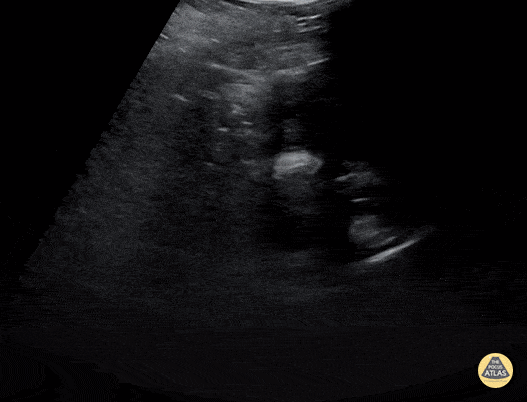

14 year old female presenting with acute on chronic abdominal pain. Physical exam revealed gross abdominal distension in the pelvic region. She denied hematuria, dysuria, or sensation of incomplete voiding. No menarche reported. In this clip, the patient's bladder is difficult to visualize due to the mass effect of the enlarged, blood-filled vagina. The uterus contains blood as well, but to a much lesser degree than the vagina. Contributor: Jaron Smith, MD Phoenix Children's Hospital